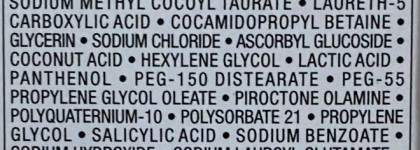

Протестирован под контролем дерматологов и офтальмологов. Без парабенов. Без силикона. Гипоаллергенный. Подходит для окрашенных волос.